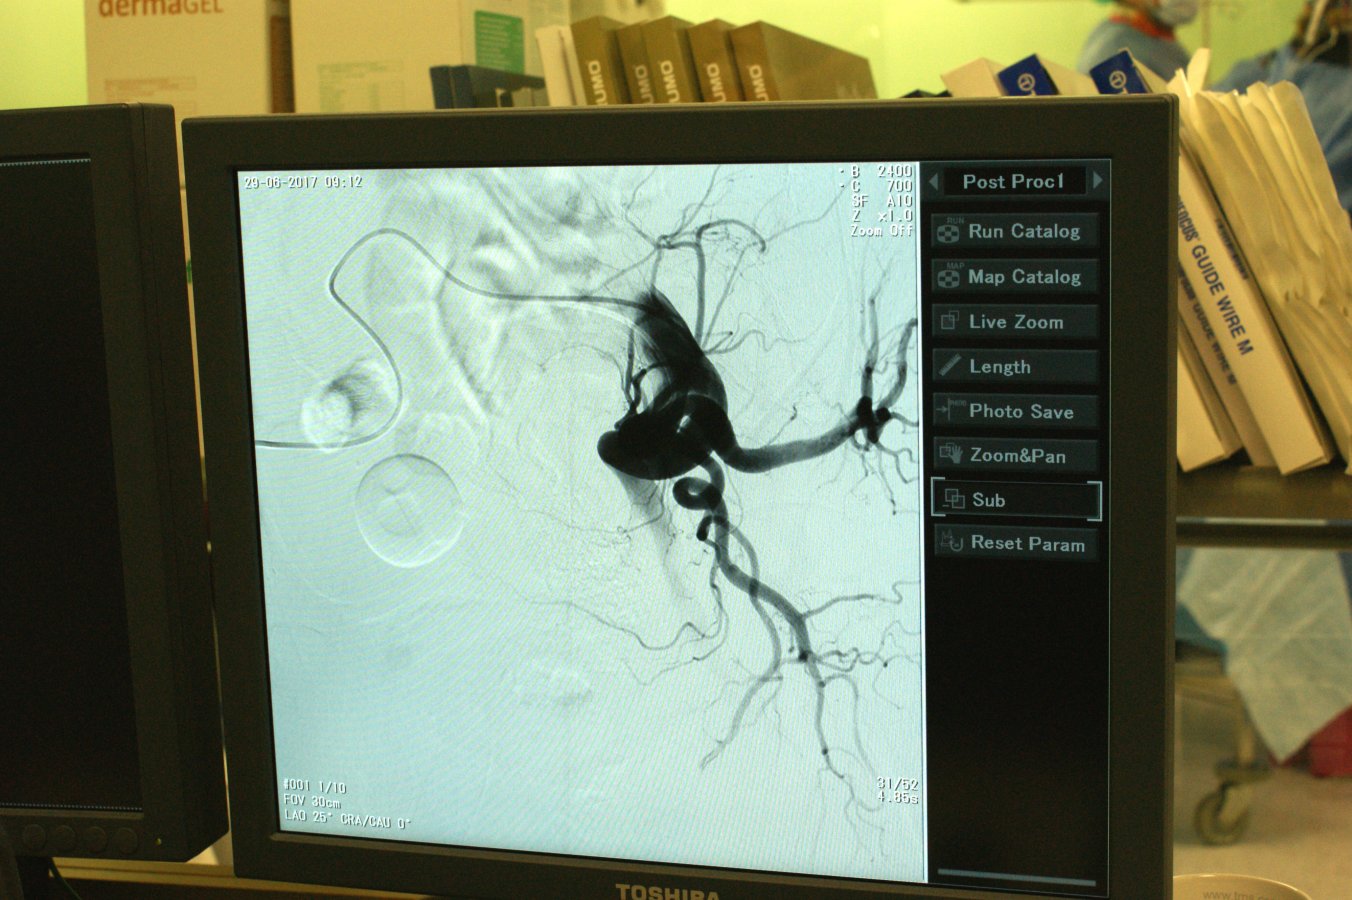

- Jeżeli o operacjach laparoskopowych mówi się, że to operacje przez dziurkę od klucza, to ta operacja jest wykonana przez ucho igielne - mówi dr Kudelski. - Przez tętnicę udową naczyniami krwionośnymi docieramy w okolicę prostaty. Wtedy do drobnych naczyń krwionośnych wprowadzamy cząsteczki, które powodują zatkanie naczyń, czyli embolizacje. W wyniku tego dochodzi do ograniczenia ukrwienia przerosłej prostaty i w konsekwencji jej zmniejszenie. Dzięki temu znika przyczyna ucisku na drogi odprowadzające mocz z pęcherza moczowego i ustąpienie uciążliwych dolegliwości.